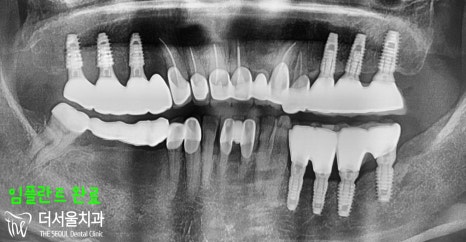

『수술 결과』

픽스처와 뼈는 골유착이 잘 이뤄져

튼튼히 고정되었습니다.

그 위에 어버트먼트와 크라운을

세팅해드렸으며,

14번 치아는 깨져있었기에

발치 후 브릿지 형태로 연결시켜

치료를 지었습니다.